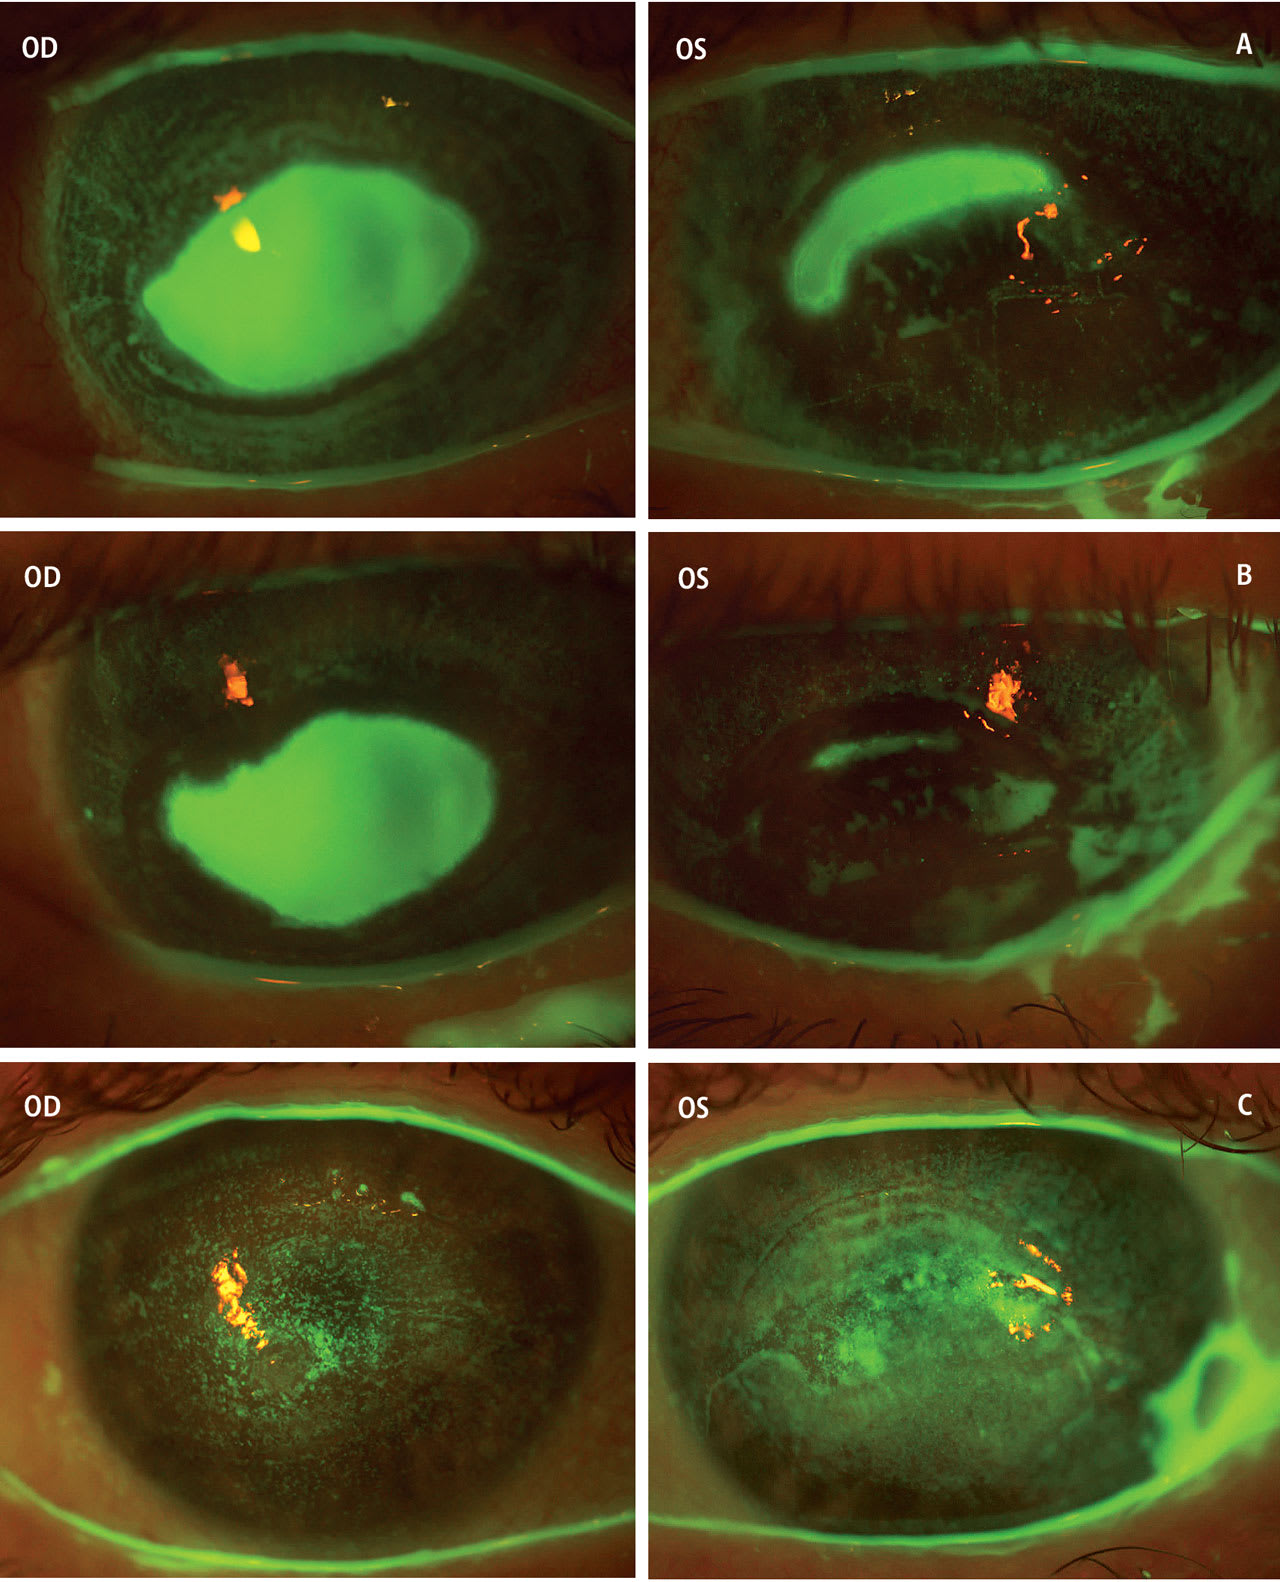

Several reports have shown the effectiveness of SLs in maintaining corneal integrity in cases of NK.29,30 Further, SLs have been utilized in severe stages of NK to encourage re-epithelialization of PED31,32,34 (Figure 6).

Unfortunately, the frequency of complications related to SL wear in NK is unknown. These may include corneal edema, sterile hypopyon, and corneal infections such as MK (Figure 7). By including a fourth-generation fluoroquinolone in the SL reservoir, cases of MK in patients being treated for PED decreased to zero in all study participants,32 compared to previous studies that resulted in MK occurring in 4/14 (29%) eyes treated without antibiotic use in the reservoir.31 This emphasizes the need for fourth-generation topical fluoroquinolone coverage with any contact lens use in cases of epitheliopathy.